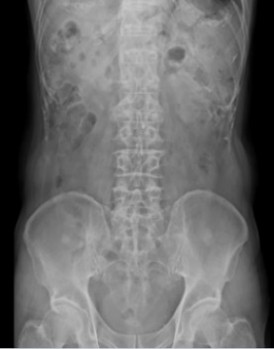

X線撮影室

胸部・腹部および全身骨部のX線撮影を行っています。